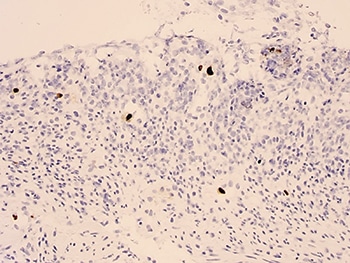

In Fig. 1 is an example of an IHC stain showing numerous inclusions. “They should be large cells with nuclear expression,” Dr. Misdraji said. In Fig. 2 is a plasma cell that shows some cytoplasmic staining. “Most people do carry CMV,” he said, but cytoplasmic staining of small lymphocytes or plasma cells, as in Fig. 2, is not indicative of active CMV disease.